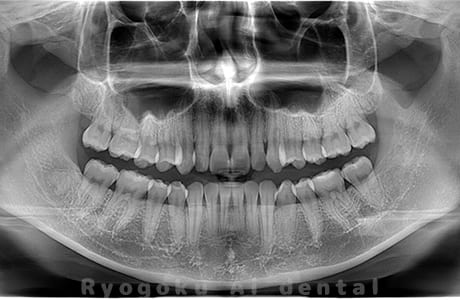

Case04

- 原因

- 上顎の親知らず、下顎の水平埋伏の親知らず

- 治療内容

- 上顎の親知らず、下顎の水平埋伏の親知らずを抜歯したケースです。

<リスク・副作用>

手術後は痛み、腫れ、痺れなどの副作用が生じる場合があります。